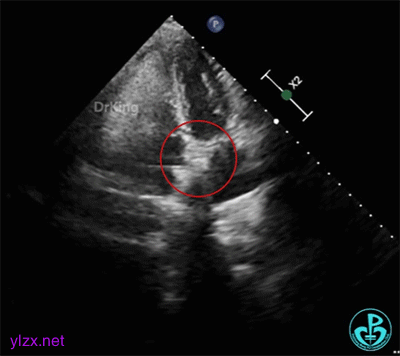

双盘展开后,经胸超声下观察血流,显示无残余分流。

释放PFO封堵器后,超声下封堵器成型良好,房间隔瘤被夹闭,封堵成功。